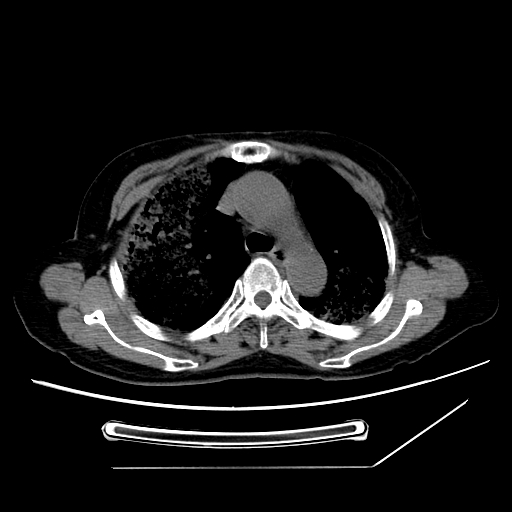

标题: CT25393:病人45岁,咳嗽,吐黄痰带血丝,发热,胸闷月余 [打印本页]

标题: CT25393:病人45岁,咳嗽,吐黄痰带血丝,发热,胸闷月余

1、左肺中央型肺癌并双肺弥漫性转移   2、双肺部感染    3、肺大泡     4、左侧胸腔积液

双侧肺弥漫性病变,可见“空泡征”及“蜂窝征”,考虑肺泡癌可能性大,左侧胸腔积液,考虑胸膜受累可能!

1)不排除肺泡癌可能。2)左侧胸腔积液。